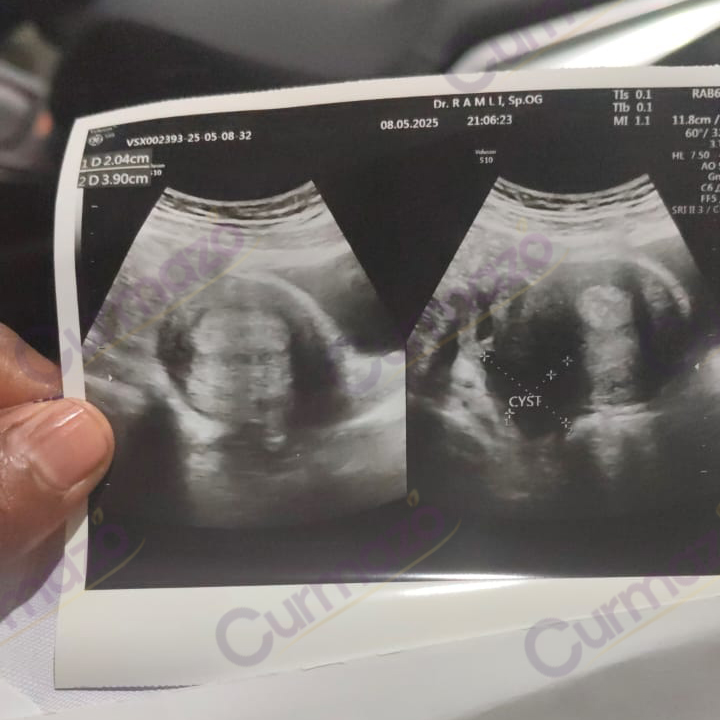

20 Maret 2025, saya periksa ke dokter ternyata ada kista di kanan kiri sebesar 6 cm. Saya menolak dioperasi karena tidak mau diangkat kantung rahimnya.

Setelah 1 bulan konsumsi, saya sudah tidak merasakan nyeri sampai tulang belakang, dan nafsu makan saya meningkat. 8 Mei 2025 saya periksa lagi, hasilnya kista 6 cm di kiri hilang total dan yang di kanan mengecil dari 6 cm jadi 2 cm.